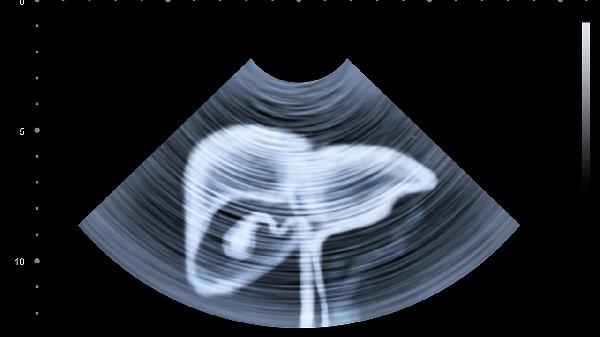

肚臍上腹部隱痛患者應注意飲食調(diào)理,選擇易消化的食物如粥類、蒸蛋、軟面條等,避免油炸食品和生冷食物。保持規(guī)律的生活作息,避免過度勞累和精神緊張。適當進行散步、瑜伽等輕度運動,促進胃腸蠕動。癥狀持續(xù)或加重時應及時就醫(yī),完善胃鏡、腹部超聲等檢查明確診斷。遵循醫(yī)囑規(guī)范治療,定期復查評估療效,切勿自行調(diào)整藥物劑量或停藥。